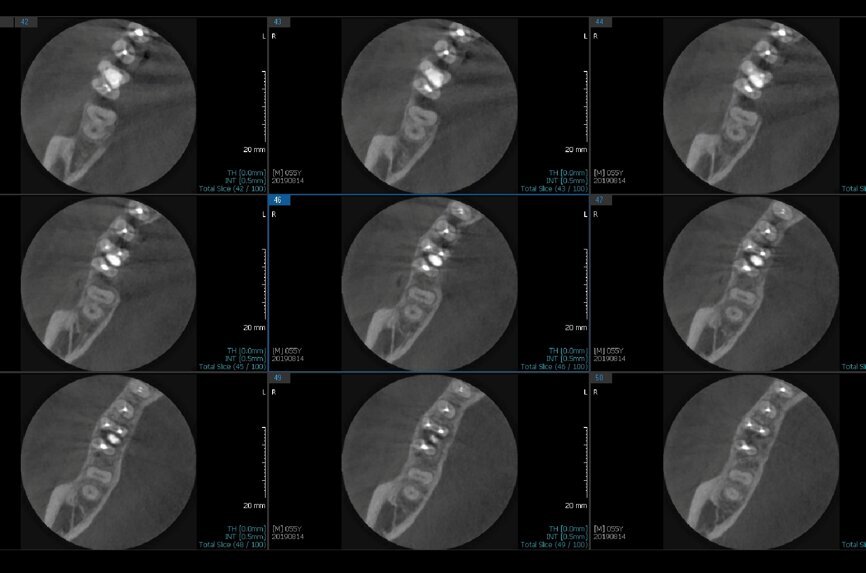

Fig.2a: Pre-op CBCT images of tooth #46: No obturation material in the distal and mesiobuccal canal (a); scanty obturation of the canals and breach of the floor of the pulp chamber, no obturation beyond a few millimetres down the orifice (b & c); radiolucency in the furcation area and periapical region of both roots (d -g).

Fig.2b: Pre-op CBCT images of tooth #46: No obturation material in the distal and mesiobuccal canal (a); scanty obturation of the canals and breach of the floor of the pulp chamber, no obturation beyond a few millimetres down the orifice (b & c); radiolucency in the furcation area and periapical region of both roots (d -g).

Fig.2c: Pre-op CBCT images of tooth #46: No obturation material in the distal and mesiobuccal canal (a); scanty obturation of the canals and breach of the floor of the pulp chamber, no obturation beyond a few millimetres down the orifice (b & c); radiolucency in the furcation area and periapical region of both roots (d -g).

Fig.2d: Pre-op CBCT images of tooth #46: No obturation material in the distal and mesiobuccal canal (a); scanty obturation of the canals and breach of the floor of the pulp chamber, no obturation beyond a few millimetres down the orifice (b & c); radiolucency in the furcation area and periapical region of both roots (d -g).

Fig.2e: Pre-op CBCT images of tooth #46: No obturation material in the distal and mesiobuccal canal (a); scanty obturation of the canals and breach of the floor of the pulp chamber, no obturation beyond a few millimetres down the orifice (b & c); radiolucency in the furcation area and periapical region of both roots (d -g).

Fig.2f: Pre-op CBCT images of tooth #46: No obturation material in the distal and mesiobuccal canal (a); scanty obturation of the canals and breach of the floor of the pulp chamber, no obturation beyond a few millimetres down the orifice (b & c); radiolucency in the furcation area and periapical region of both roots (d -g).

Fig.2g: Pre-op CBCT images of tooth #46: No obturation material in the distal and mesiobuccal canal (a); scanty obturation of the canals and breach of the floor of the pulp chamber, no obturation beyond a few millimetres down the orifice (b & c); radiolucency in the furcation area and periapical region of both roots (d -g).

When I had a close look at the preoperative radiograph from the referring dentist (Fig. 1a), I observed that there was insufficient obturation of the mesial canals and almost no obturation of the distal canal. Both roots displayed periapical radiolucency. The clinical examination revealed a Grade I mobility, and the tooth was tender to percussion. The periodontal examination ruled out any pockets and loss of attachment. We took an intra-oral periapical radiograph (Fig. 1b), from which we observed the loss of coronal structure and a large radiolucent area over the furcation area and the periapical area of both the mesial and the distal roots. A CBCT scan of tooth #46 was advised to check for any details that may have been missed in the intra-oral periapical radiograph (Figs. 2a–g). From the CBCT scan, it could be observed that there was inadequate obturation of the distal canal on the horizontal plane, no obturation beyond the middle third in the mesial canals and a breach of the floor of the pulp chamber. The questionable prognosis was explainedto the patient, and written consent was obtained.